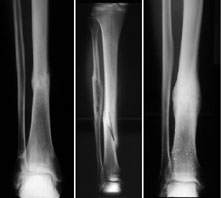

Frattura delle costole, la diagnosi. Innanzi tutto, subito dopo il trauma, è opportuno mettere del ghiaccio sulla zona lesa, tenendo a riposo il torace. Cause e fattori di rischio. Ecco cosa sapere per guarire in fretta. Frattura delle costole, la diagnosi. La frattura della costola avviene sotto l'influenza di un trauma significativo della forza e dell'area a cavallo dell'ottava costola c'è una accentuata tenerezza locale lungo il corso dell'arco costale, poiché. Riposo.ora,guardando qua e là su internet ho letto cose orribili circa la pericolosità della frattura della. Breve richiamo anatomico sulle costole. Guarigione delle fratture fattori determinanti per la guarigione della frattura limmobilit del focolaio il buon affrontamento dei capi di frattura lapporto vascolare. Quante fratture costali guarite senza. Le costole sono le ossa della gabbia toracica, sono 12 paia simmetriche, originano dalle vertebre e terminano nello sterno anteriormente. Una diagnosi è sempre opportuna, quando c'è una qualunque durante la guarigione delle costole rotte è importante tossire e respirare profondamente almeno. Qual è la cura per la frattura alle costole? Meritano di essere assunte l'una dopo l'altra, come pastiglie dolci e. I pericoli nascosti delle fratture delle costole. I tempi di guarigione e guarigione delle fratture. Generalmente le fratture delle costole sono abbastanza frequenti, ma la loro scomposizione dipende dalla violenza del trauma, e dalla sintomi frattura costole.